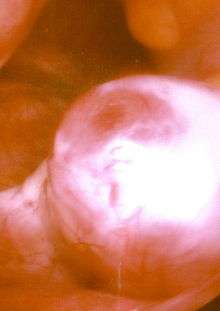

An ovary about to release an egg